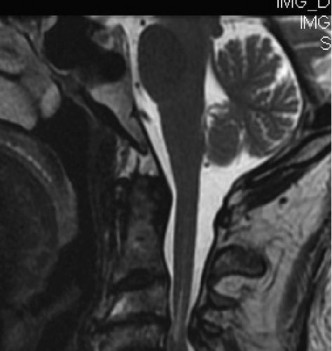

A 63-year-old male sustained a hyperextension injury to his neck while diving into a pool. Upon presentation, he reports decreased sensation in his hands and decreased strength in his arms and wrists, but no lower extremity complaints. On motor examination, he has 5/5 strength in his deltoids and elbow flexors and 4/5 strength in the elbow extensors, wrist extensors, and finger flexors. Lower extremity motor examination is normal. Sensation is decreased to light touch in both hands. Otherwise his sensation is preserved. Images of his cervical spine are shown in Figures 1–1 to 1–3.

Figure 1–2

The correct answer is (B). The clinical scenario describes a patient with central cord syndrome (CCS). CCS continues to be the most common incomplete spinal cord injury accounting for 15.7% to 25% of all spinal cord injuries. The characteristic presentation is an extension moment injury in a previously spondylotic and stenotic spine. Figures 1–1 to 1–3 demonstrate a spondylotic spine with central narrowing and CSF effacement that is worst at the C3–4 level. Bleeding, edema, and/or Wallerian degeneration lead to damage of the lateral corticospinal tract which is the main descending motor tract in the spinal cord. The more central anatomic position of the homunculus to the upper extremities places them at greater risk than those to the lower extremities. As such, injury to the lateral corticospinal tract is characterized by upper more than lower extremity involvement and motor deficits being more pronounced than sensory deficits.